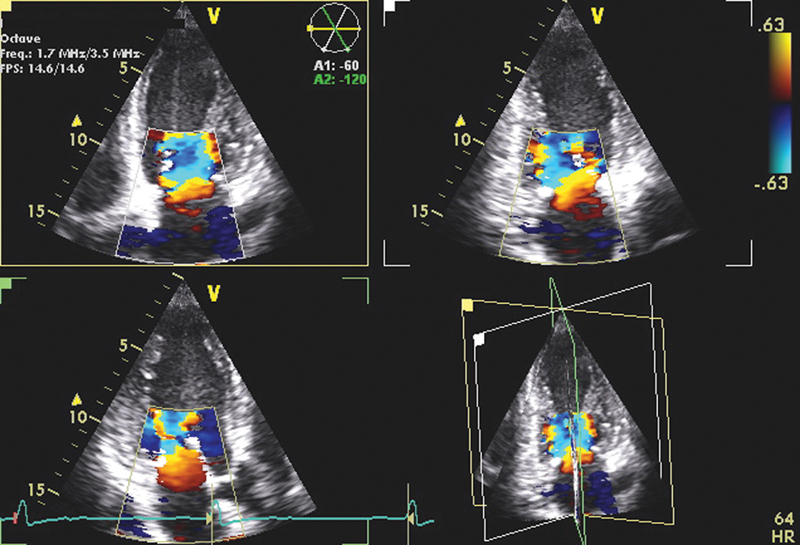

فحوصات تشخيصية لبعض امراض القلب والشرايين التاجية